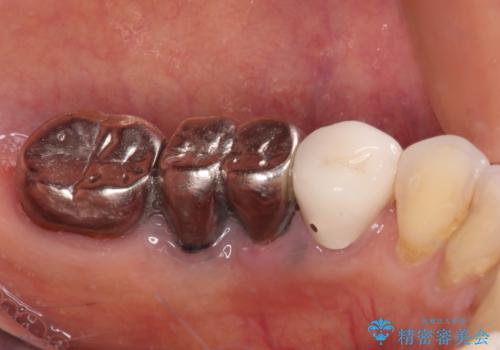

- 以前抜歯を回避するために奥歯を分割して保存してもらったものの、痛みと異臭が気になるとのことで来院された患者様です。

診査したところ、保存は不可能と診断しました。

前後の歯も大きな銀歯が装着されていたので、抜歯後に治癒を待って、フルジルコニアブリッジにて補綴することとしました。